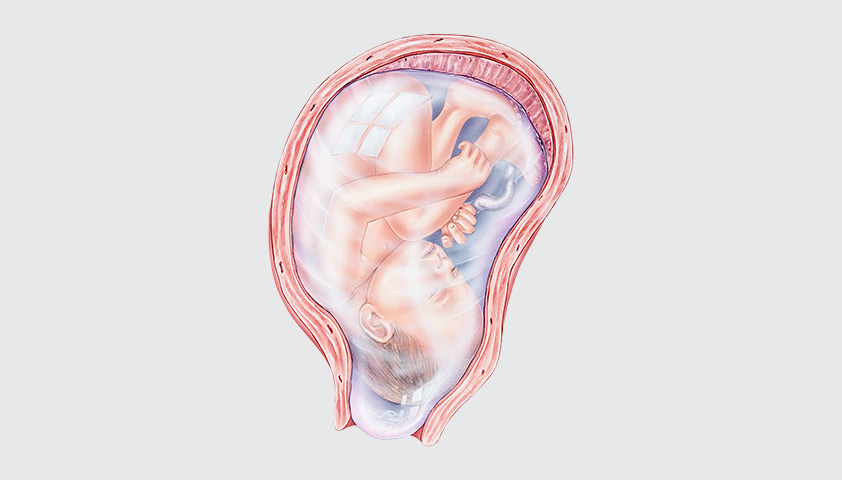

Амнион и Околоплодные Воды: Функции и Роль в Беременности